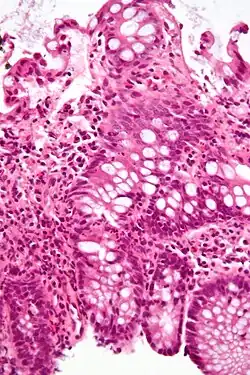

An important investigation in the assessment of colitis is biopsy for histopathology. A very small piece of tissue (usually about 2mm) is removed from the bowel mucosa during endoscopy and examined under the microscope by a histopathologist. A biopsy report generally does not state the diagnosis, but should state any presence of chronic colitis, give an indication of disease activity, as well as state the presence of any epithelial damage (erosions and ulcerations).[6]

Histopathology findings generally associated with chronic colitis include:[6]

Crypt degeneration -

Crypt branching and other architectural distortions -

Paneth cell (pictured) or gastric metaplasia (only applies in the left colon and rectum)

Other findings include basal plasmacytosis and mucin depletion.[6] Histopathology findings generally associated with active colitis include:[6]

-

Neutrophilic cryptitis (neutrophils within crypt epithelium) -

Crypt abscesses (luminal neutrophilic aggregates) -

Gland destruction -

Ulceration (seen here as absence of epithelium, and granulation tissue with many fibroblasts)